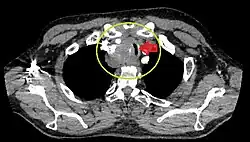

Rétrécissement trachéal (flèche rouge). Tomodensitométrie (coupe transversale).

Même tumeur (coupe sagittale).